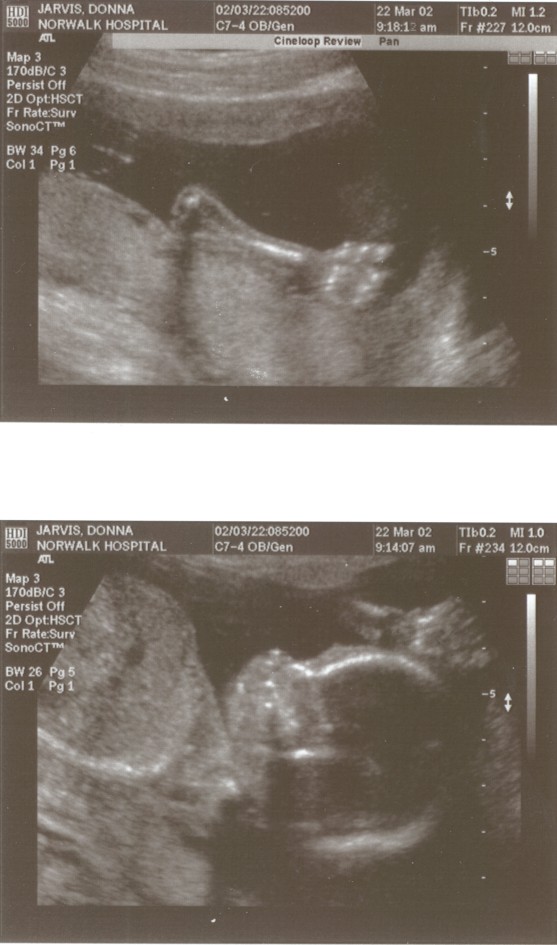

6/15/02 (Week 32)- We had our last ultrasound this week. The baby appears in good health and is estimated at 3 pounds, 14 ounces which is around the median size. We saw her lips and her tongue and watched her yawn. We also saw her little heart beating and watched her kick. Mom, however, is getting more and more uncomfortable - back aches, feet hurt, hands, feet and legs swollen. And she gained a little too much weight this visit, so we are now watching what we eat. We picked out our baby announcements this week and the room will finally be painted next week, so we are making some progress on getting everything done before the baby arrives!